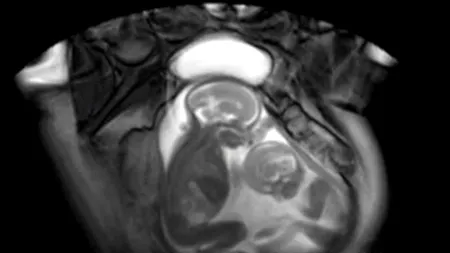

VIDEO. Cum se

02 dec. 2012, 17:02

VIDEO. Cum se „bat” gemenii în pântecele mamei